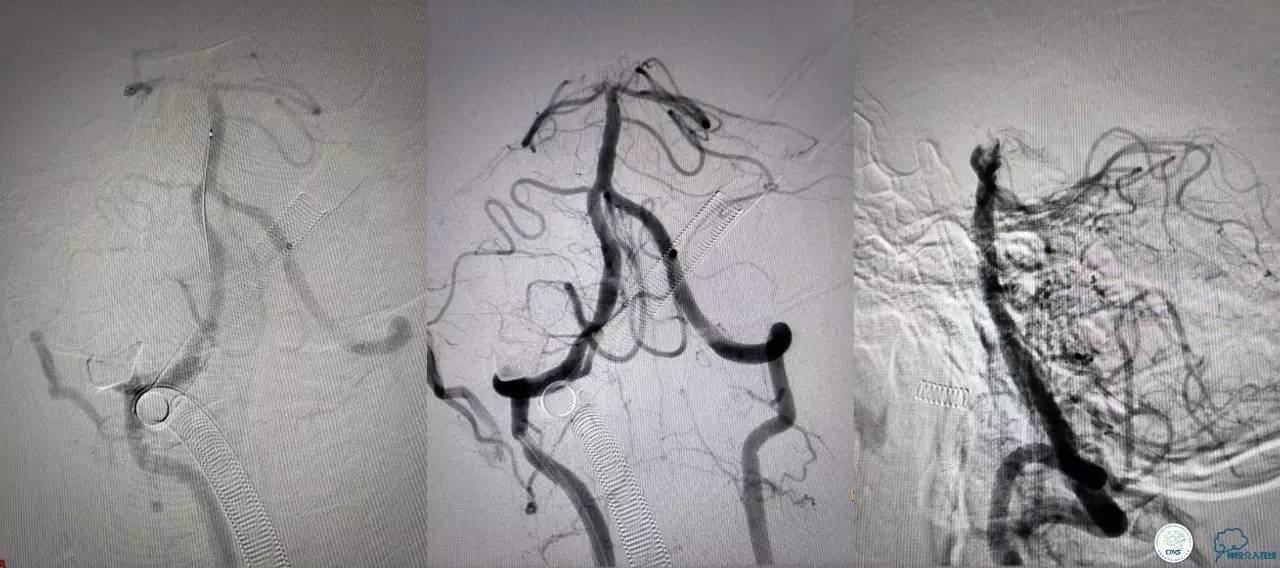

基底动脉顶端仍有大量血栓,双侧大脑后动脉未见显影,双侧小脑上动脉再通。再次取栓?还是动脉溶栓?

决定导管内给予替罗非班6ml,复查造影BA顶端仍闭塞,第二次取栓。

第二次取栓后可见基底动脉顶端仍有大量血栓,右侧大脑后动脉开通,但左侧大脑后未见显影且左侧小脑上动脉闭塞!

第三次取栓,支架放入左侧大脑后取栓。

第三次取栓后,左侧大脑后动脉开通,但是栓子再次栓塞右侧大脑后动脉,血栓在基地动脉顶端来回左右摆动,下一次,怎办?血栓负荷太多,可以使用solumbar技术,可以没有颅内导管,没办法,换用更大的支架6-20mm,但费用增加不少,与家属沟通后同意使用,第四次取栓:

血栓负荷还是很大,左侧大脑后再通,但右侧大脑后又闭塞,只能第五次取栓,支架放到右侧大脑后动脉更远。